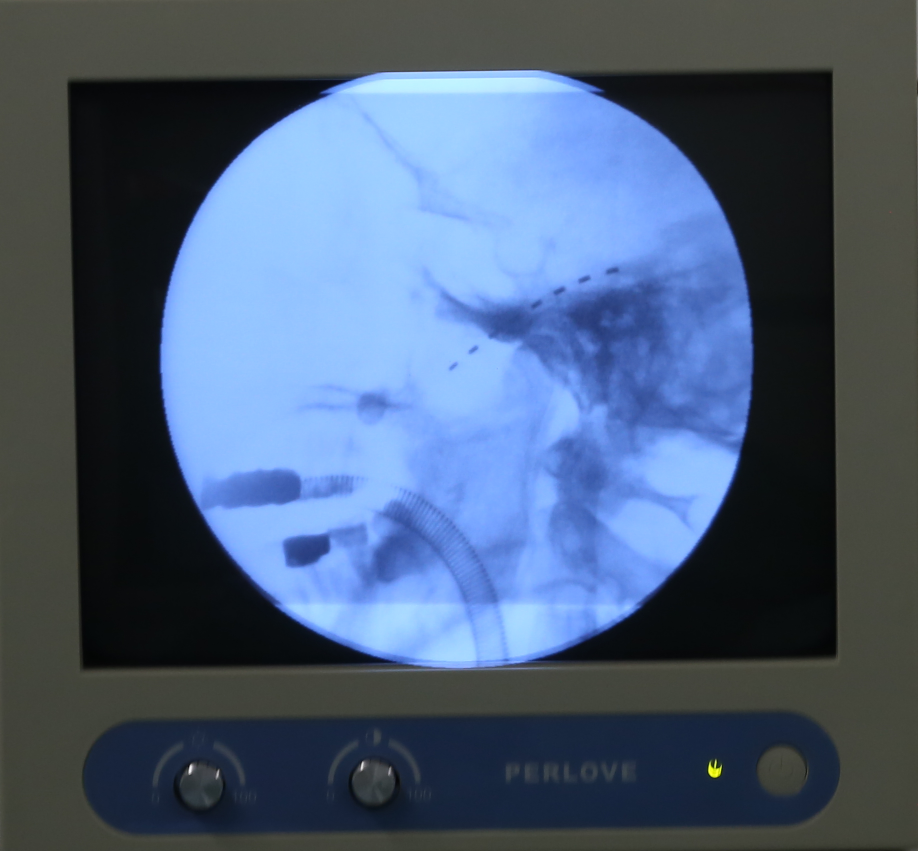

11月27日,四川省人民医院赵冬冬主任联合麻醉手术科,为李大爷实施了院内首例三叉神经半月节电刺激装置植入术。术中X线透视下精确定位,精准穿刺,将电极置入三叉神经节附近,X线透视可见电极置入位置准确,且未出现并发症,手术微创、无痛、安全、有效。

术后医生通过测试刺激器为李大爷调适靶点位置和电压参数